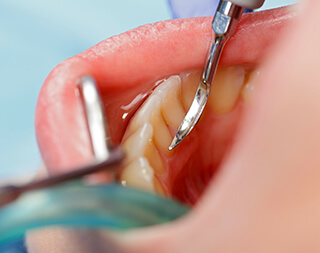

SRPとはスケーリング&ルートプレーニングの略で、 専用の器具を使用して、病原性の高い歯石を取り除く処置です。歯周病治療の1つで、ハンドスケーラーと呼ばれる専用の器具や、超音波の器具を用いて歯周ポケットの中(歯ぐきの中の歯の根に隠れている部分)の歯垢(プラーク)や歯石を取り除き、汚染された根面のセメント質や象牙質を除去してなめらかな根面にすることです。